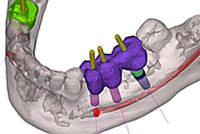

3次元シミュレーション シムプラント

シムプラント(SimPlant)は、CT撮影のデータを再構成した3D画像により、多角的な測定やインプラント埋入シミュレーションを実現します。

下顎管は線描画機能で見やすく表示し、埋入位置までの距離や頬舌的位置が的確に把握できます。

上顎では、複雑な骨形態が明確になるだけでなく、上顎洞炎、嚢胞、粘膜肥厚なども術前に発見しやすくなります。さらに、ソケットリフトやサイナスリフトなどの骨造成治療に必要な骨体積も計算できます。

3Dの立体画像により、分かりやすくご理解いただけます

CT撮影した顎や歯のデータをもとに、さらに詳しい3Dの立体画像で解析し診断使います。インプラントの安全性を語る上でもっとも気を付けなければいけないポイントが神経の位置、血管の位置、上あごにある空洞の位置です。例として、

- 下顎の神経がインプラントを埋入する位置に非常に近い場合

- 上顎の骨が薄く、空洞(上顎洞)に骨造成しないといけない

…等々のようなケースにおいては、術前シミュレーションでより安全な手術を実現することができます。

3Dによる立体画像で、顎の骨の状態が、見た目にも分かりやすくご説明できることと、ドクターにとっても手術のイメージがよりつかめるメリットがあります。